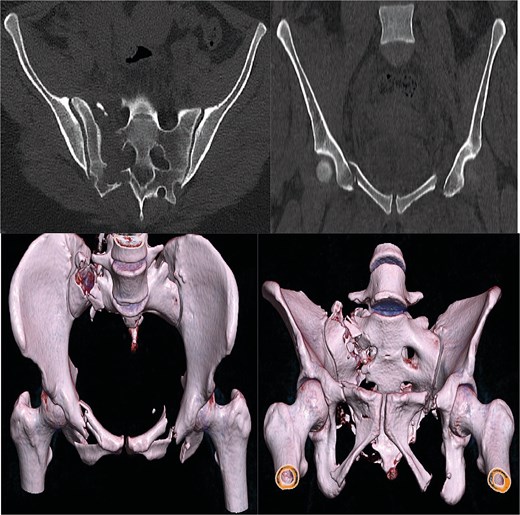

A 30-year-old female patient was admitted to the emergency department after falling from a truck and subsequently being run over by the same vehicle. Initial assessment revealed polytrauma with an unstable pelvic ring fracture and vaginal laceration, characterizing an open fracture. Imaging studies, including X-rays (Fig. 1) and computed tomography (Fig. 2), confirmed a Tile C3 fracture with bilateral vertical instability, classified as a lateral compression type III according to Young-Burgess [3]. Additional findings included a sacral fracture in Denis zone 2 on the right, disruption of the left sacroiliac joint, a mild right-sided pneumothorax, and a mild abdominal contusion. The vaginal laceration, ⁓5 cm in length, was successfully sutured by the gynecology team in the emergency room, with no immediate signs infection. The Injury Severity Score (ISS) was estimated at 33, reflecting the severity of the polytrauma (Table 1). Although hemodynamically stable, the patient was to the intensive care unit (ICU) for hemodynamic monitoring due to the risk of instability.